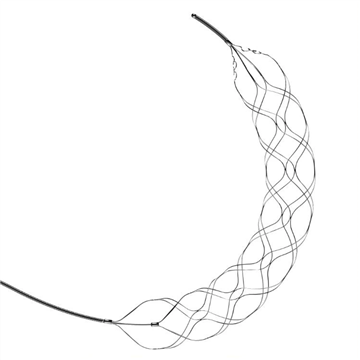

Stent Retriever za trombektomijoStent retrieverji so endovaskularne naprave, ki lahko odstranijo strdke iz velikih arterij pri bolnikih z akutno ishemično možgansko kapjo. Te naprave so zasnovane tako, da se dovajajo skozi kateter v

Kaj je stent retriever trombektomija?Trombektomija s stentom je minimalno invaziven kirurški poseg, ki se uporablja pri zdravljenju ishemične možganske kapi. To je oblika nevrovaskularnega posega, ki vključuje uporabo naprave za pridobiv

Intrakranialni stent retriverNa trgu je razkrita naprava za odstranjevanje strdkov, ki jo je mogoče uporabiti v intrakranialnih krvnih žilah in vključuje okostje, ki ga je mogoče spletati iz žic iz zlitine s spominom oblike, da z